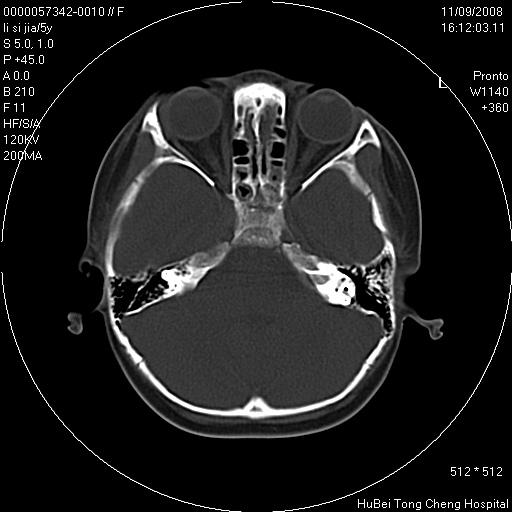

患儿 女,5岁。鼻塞、流涕2年余。

临床诊断:慢性副鼻窦炎?

副鼻窦ct轴位平扫(层厚、层距均为5mm),图像如下:

双侧上颌窦\\筛窦及蝶窦内均可见多量软组织密度影,结合病史支持考虑慢性全鼻窦炎

双侧上颌窦、筛窦及蝶窦内均可见粘膜增厚,结合病史支持考虑慢性全付鼻窦炎,腺样体肥大。